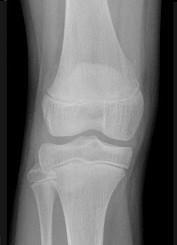

女,请根据其正常膝关节影像图像,判断其最可能的年龄 ( )A、23岁左右B、29岁左右C、11岁左右D、17岁左右E、5岁左右

问题 女,请根据其正常膝关节影像图像,判断其最可能的年龄 ( )

选项 A、23岁左右 B、29岁左右 C、11岁左右 D、17岁左右 E、5岁左右

答案 C